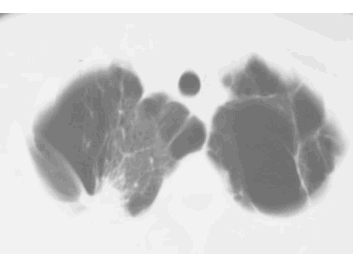

How would you describe the LUNG abnormality in each of these cases?

B